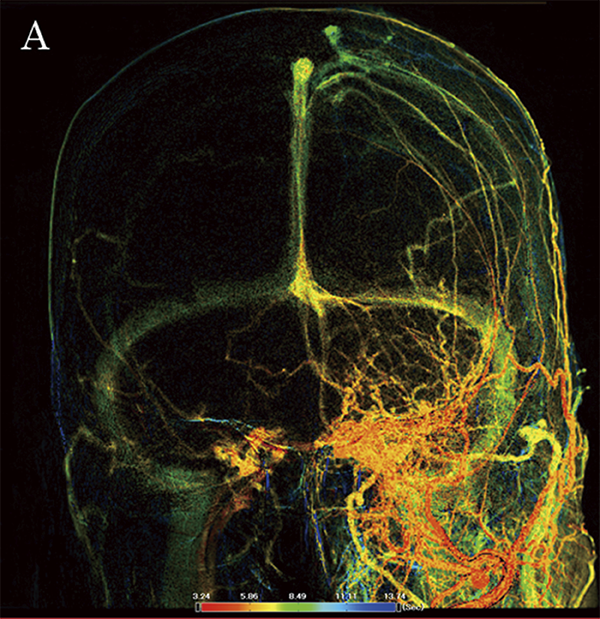

Новий параметричний метод кольорового кодування зображення (Color Coded Circulation, CCC) (малюнок 10A та 10B) дозволяє спостерігати за змінами кольору на динамічному зображенні, що полегшує розуміння напрямку кровотоку. Зображення CCC можуть бути створені автоматично, після DSA, що дозволяє спостерігати за змінами кровотоку під час процедури. У цьому випадку передопераційна DSA чітко продемонструвала ретроградний потік до поверхневої середньої мозкової вени (SMCV) та мішечок, у якому сходилися точки шунтів, що було підтверджено CCC (малюнок 10A та 10B, жовта ROI). Фідер був націлений з лівого кавернозного синуса (CS) і висхідної глоткової артерії (AphA). Фідер на лівій середній менінгеальній артерії (ММА) заклали спіралями. AphA емболізували, а потім через нижній кавернозний синус (ICS) емболізували ділянку від лівого CS до місця злиття з правим CS. Процедуру було завершено після підтвердження антеградного кровотоку у верхній очній вені (SOV) і SMCV.

Малюнок 10A: ССС зображення CSdAVF (вид спереду). Жовта досліджувана ділянка: сумка, біла лінія: MMA – фідер

Малюнок 10B: ССС зображення CSdAVF (вид збоку). Жовта досліджувана ділянка: сумка для шунта, біла лінія: MMA – фідер

«CCC забезпечує чудову візуальну підтримку, а зображення можна реконструювати в режимі реального часу. Оскільки цей функціонал використовує раніше отримані зображення DSA, він не потребує додаткового введення контрастної речовини або рентгенівського опромінення. Ми вважаємо CCC надзвичайно корисним».

– Доктор Сатов.